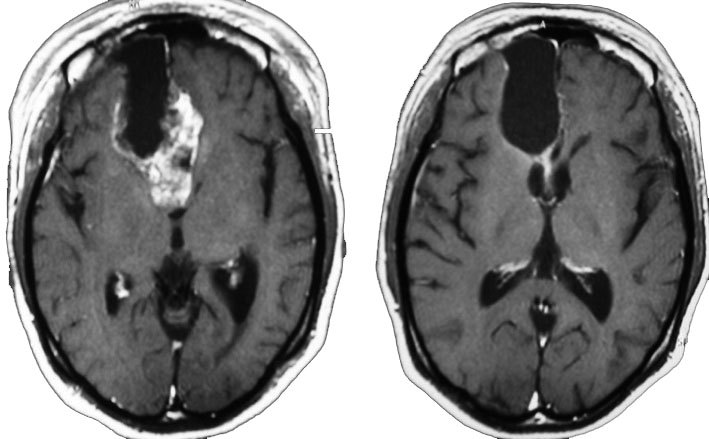

左は術後のT1強調ガドリニウム増強像で,残存腫瘍がわかります。この腫瘍に対してICE (IFO/CDDP/VP-16) 化学療法を1コースしました。右側のMRIが1ヶ月後の画像です。このように1p/19q欠失のある退形成性乏突起膠腫は,化学療法感受性がとても高い悪性グリオーマです。ですから,手術で後遺症を残さないように,勢い込んで腫瘍を摘出しようとしないことが大切です。光顕診断はAOで,後々の解析で1p/19q codeletion でした。